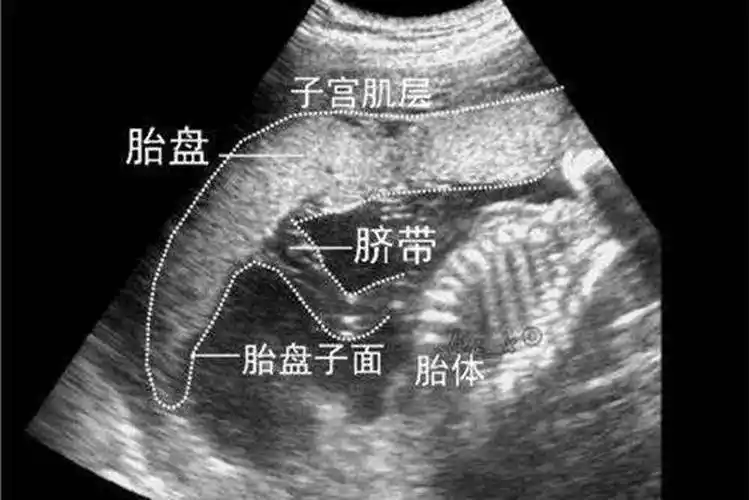

原创怀孕第几个月胎盘固定不是3个月也不是5个月